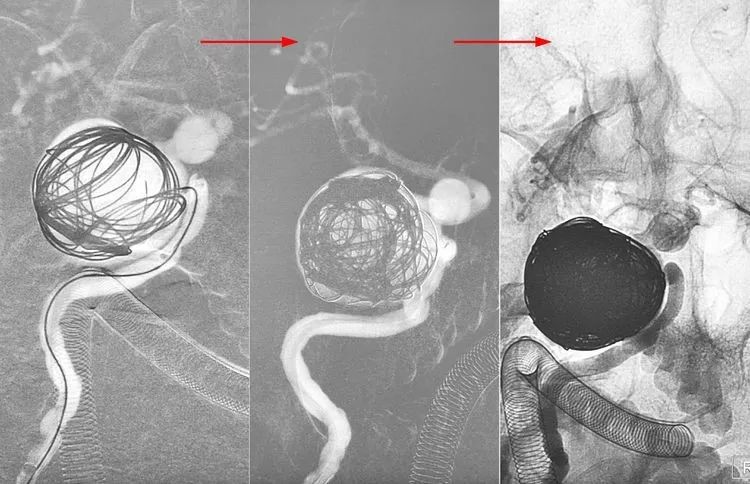

计划不如变化,决定一期先用弹簧圈填塞大瘤,隔至少一个月后再二期置放密网支架。双微管依次、交替填入11枚弹簧圈(MicroPlex 18-24-68-Cosmos Complex 九枚,MicroPlex 18-20-65-Cosmos Complex,QC-20-50-3D),部分栓塞大瘤。

术后右颈内动脉各角度造影显示大瘤部分栓塞,载瘤动脉畅通,希望通过一段时间的血流冲击使大瘤内的弹簧圈夯实,为二期支架导管的通过提供铺垫和支撑。

1个半月后二期行密网支架置入。

5F Navien中间导管置入右颈内动脉岩骨段,行右颈内动脉造影显示大瘤大部栓塞,瘤颈处开放。